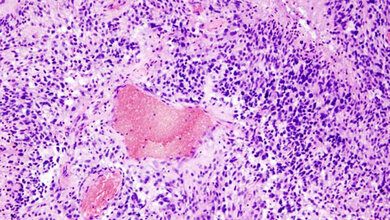

Menschen, die Träger von Genmutationen an BRCA1 und/oder BRCA2 sind, haben ein sehr hohes Risiko für bestimmte Tumorarten, allen voran für Brust-, Eierstock- und Prostatakrebs. Ihnen fehlt eines dieser Werkzeuge – deshalb entstehen öfter Krebszellen. Zwar haben auch diese Tumorzellen nur ein Tool zur Verfügung, um ihr Überleben zu sichern: PARP1. Dennoch sind gerade BRCA1/2 assoziierte Tumore meist sehr aggressiv und schwer behandelbar. Forscherinnen und Forscher um Professor Claus Scheidereit vom Max Delbrück Center und Letztautor der Studie, haben sich deshalb den Signalweg, der das Enzym PARP1 aktiviert, genau angesehen. Dabei entdeckten sie einen Weg, dieses Werkzeug gezielt unbrauchbar zu machen.